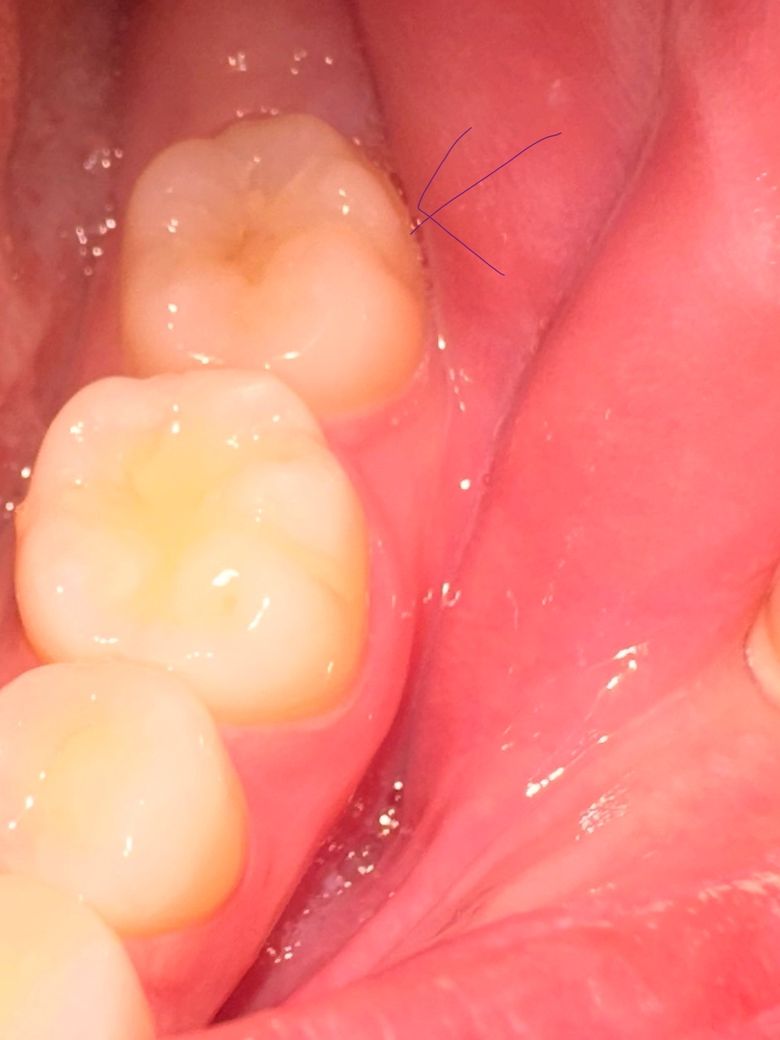

저기 맨 뒤 이빨입니다. 저번에도 이런적이 있어서 치과를 갔는데 충치는 없다고 하더라구요. 반년이상이 지나고 최근들어 또 뭔가 미세하게 시린 느낌이 나서,, 신경도 쓰여서 괜히 아픈 느낌이 들고 충치 맞나요? 맞으면 초기 인가요? 충치치료 아플까요?

• 1번 째 사진

사진에 보이는 부분에 잇몸이 안좋은거 같습니다. 일단은 잇몸치료를 먼저 받아보시는게 좋을것같습니다.

사진 상으로는 충치가 의심되지는 않습니다. 시린 증상 지속시엔 치과에서 검사 받아보시는 게 좋겠습니다.

사진으로만 봤을경우 크게 문제가 있는것으로 보이지는 않습니다 이런경우 치아에 너무 강한힘이 가해지는 것일 수도 있으니 치아에 가해지는 힘을 줄여주는 것이 좋습니다

외견상 충치은 없어보이고 단지 치태및 치석이 다소 끼어있으니 치과가서 스케일링 한번 받으시기 바랍니다